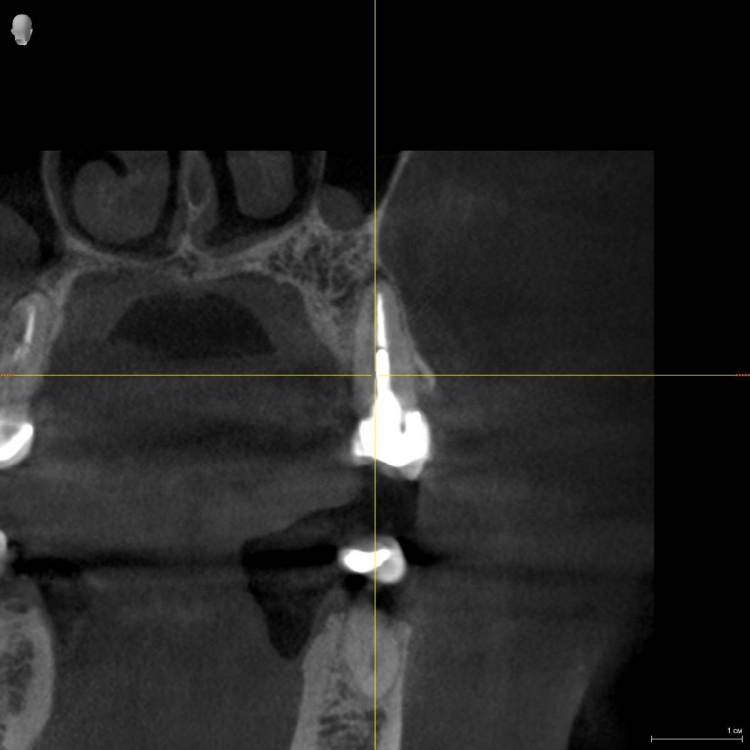

Три месяца назад стала болеть десна верхнего зуба возле коронки (пятый), только с внутренней стороны , но при этом все время языком хотелось трогать соседний зуб( 4). Врач ничего не увидела, сказала полоскать. На давление, холод, постукивания зуб с коронкой и соседние не реагировали. Через какое то время возникло ощущение что 4 верний зуб как будто вырос и немного подвижет, на что врач ответил что я выдумываю, предложил поменять пломбы на соседних зубах, но лучше не стало. Сделала КТ, опять ничего не видят. Ко всему этому добавилась головная боль и усталость. на десне, с внутренней стороны, выше к нёбу между 6 и 7 зубами  выскочила шишка,если сильно нажать то болит, а так нет, выделений нет.  сделали рентген, опять мне говорят, что все ок. На мой вопрос , что это за круги на рентгене, ничего не ответили, к сожалению забыла взять последнюю фото, но на первом прицельном фото этот круг уже виден, на новом больше кругов и они распространились дальше на 6, 7   зубы. На панорамме видно как новооброзование. Погите понять что это?

Прицельное фото в марте  делала, КТ в мае. А новое фото забыла взять.

Iljaseviciene_Lina_3D-обследование(1)_VO1_20210507_090920_Трансверсальная проекция.jpg